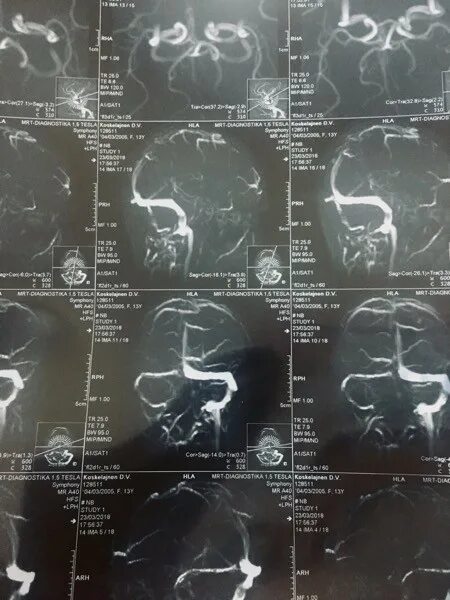

Синусы мозга мрт